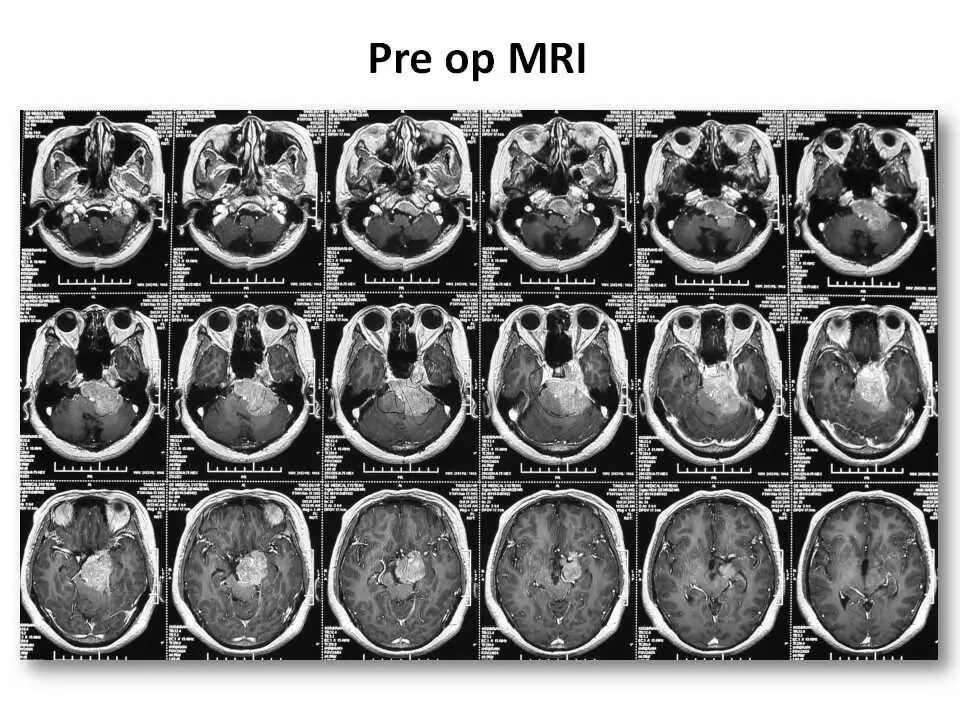

此处我们分享一例采用经典乙状窦前入路切除巨大岩斜脑膜瘤的病例。由于患者术前听力已经丧失,故我们磨除了患侧半规管,以求更好的暴露肿瘤中线斜坡基底、特别是中线对侧部分肿瘤的基底。不当之处,请批评指正!